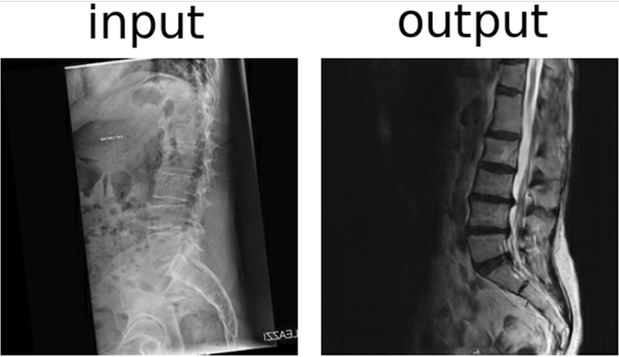

New innovative technology, deep learning, is revolutionising many research and industrial fields. Growing interest in generative models inspired the authors to explore their potential in the field of magnetic resonance imaging of the spine. Tests showed that the performance of the models was generally positive and promising, albeit several limitations should be taken into account.

Article: Generative models: an upcoming innovation in musculoskeletal radiology? A preliminary test in spine imaging